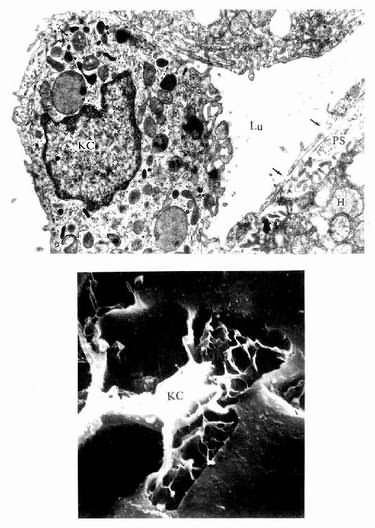

肝巨噬细胞:又称枯否细胞(Kupffer cell),是定居在肝内的巨噬细胞。细胞形态不规则,有许多板状或丝状伪足,细胞表面有许多皱褶和微绒毛,并有较厚的糖衣。细胞常以其伪足附于内皮细胞上或穿过内皮细胞窗孔或细胞间隙伸入窦周隙内(图13-16)。胞质内溶酶体甚多,并常见吞噬体残余体。肝巨噬细胞来自血液单核细胞,是体内固定型巨噬细胞中最大的细胞群体。肝巨噬细胞具有变形运动和活跃的吞饮与吞噬能力,构成机体一道重要防线,尤其在吞噬清除从胃肠进入门静脉细菌病毒和异物方面起关键作用。肝巨噬细胞还可监视、抑制和杀伤体内的肿瘤细胞,尤其是肝癌细胞,并能吞噬和清除衰老、破碎的红细胞血小板等。此外,肝巨噬细胞还有处理和传递抗原、诱导T细胞增殖及参与调节机体免疫应答等作用。

肝巨噬细胞(KC)电镜像

图13-16 肝巨噬细胞(KC)电镜像

上图 大鼠肝 ×24000(上海医科大学电镜室供图)

Lu血窦腔,H肝细胞,PS窦周隙,↑内皮细胞孔

下图足月胎儿冷冻割断扫描电镜像

(河北医学院吴淑兰教授供图)